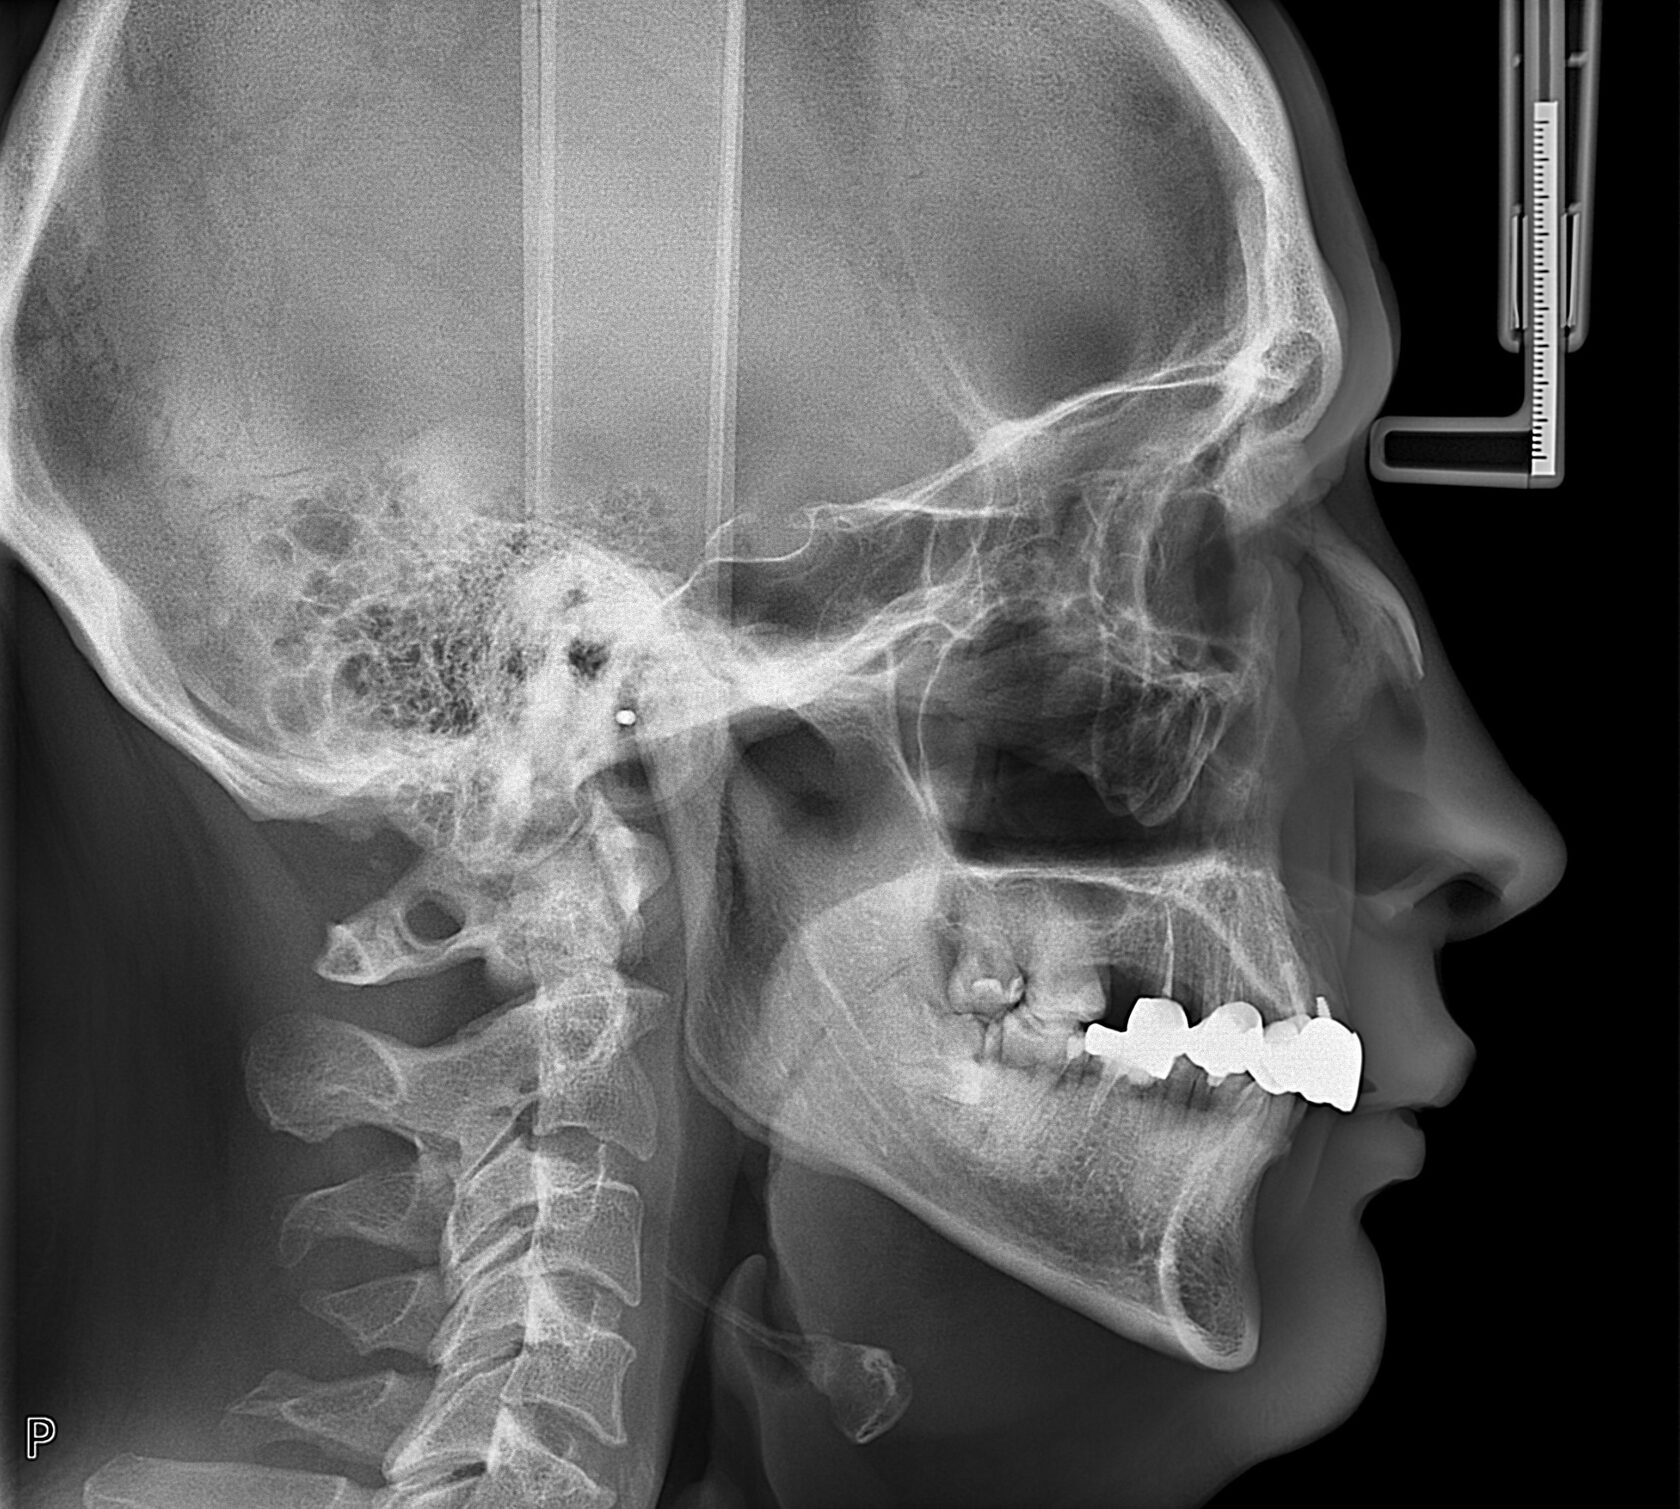

Двухмерный снимок черепа, позволяющий провести анализ соотношения челюстей, наклон зубов и выявить аномалии прикуса.

Сроки готовности цефалометрического анализа до 5 дней. Срочные — на следующий день.

Набор скриншотов без заключения врача-ортодонта.

Набор скриншотов и заключение врача-ортодонта.

Набор скриншотов и заключение врача-ортодонта + описание ВНЧС.

Набор скриншотов и заключение врача-ортодонта + описание ВНЧС + описание всех патологических изменений зубочелюстной системы.

Расчет по методике 3D Центра (Kim, Jabarak, McNamara, Ricketts, Sassouni). Интерпретация результата.